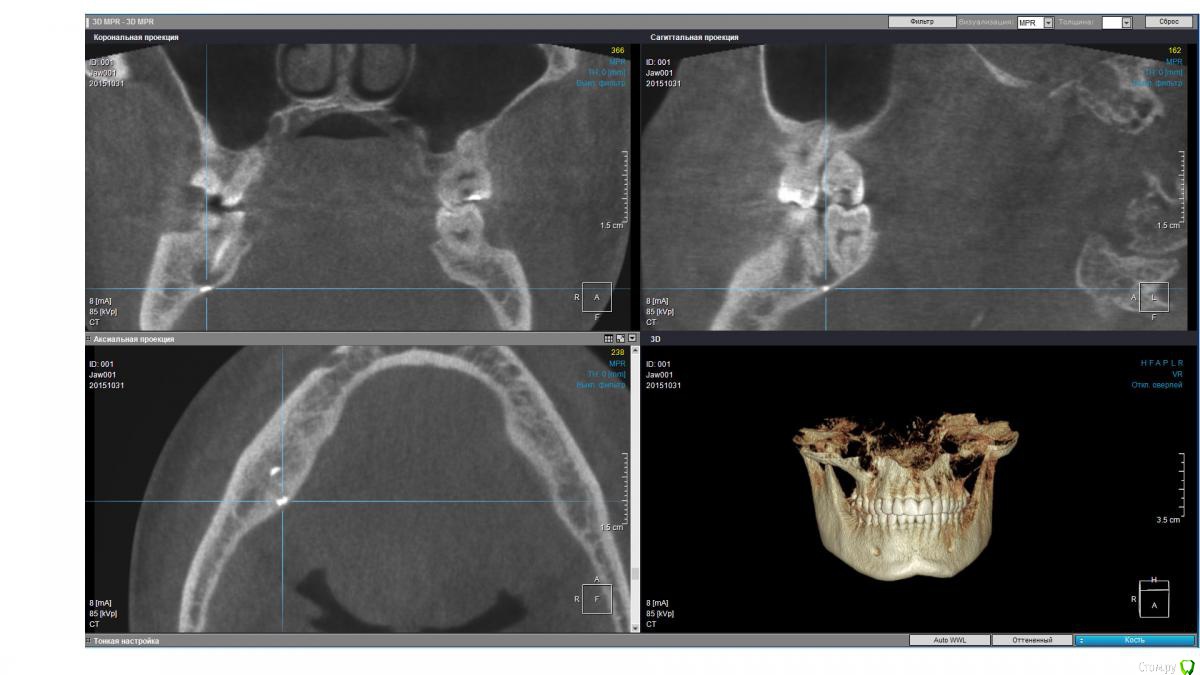

isubru Опубликовано 31 октября, 2015 Поделиться Опубликовано 31 октября, 2015 (изменено) Здравствуйте, Депульпировали зуб, потом он болел где-то с год. Больно было сильно надкусывать, потом боль прошла. "Смеркалось". Через какое-то время на десне сформировался "гноепровод". Постоянно что-то течет. Зуб предлагают удалять (должен сказать, что эта процедура настолько тут в ходу, что на неё всех поголовно отправляют). Сделал КТ. Под 47 действительно 2 кисты, но что интересно на дне полостей какие-то плотные нитевидные "обломки" в 2.5-2.8мм длинной и 1мм в диаметре. Буду очень признателен совету, как мне избавится от этой напасти. Зуб, видимо, уже не спасити?31 ноября 2015 Чуть менее годом ранее. Изменено 31 октября, 2015 пользователем isubru Ссылка на комментарий

DmitrySH Опубликовано 31 октября, 2015 Поделиться Опубликовано 31 октября, 2015 Если только на основании данного КТ, то есть шансы и спасти.На КТ фрагментов инструмента не увидел. Есть какие-то точки. Но надо понимать, что пломбировочным материал, инструменты и тп в каналах сильно "фонят" на КТ. Прицельные снимки есть? Ссылка на комментарий

isubru Опубликовано 31 октября, 2015 Автор Поделиться Опубликовано 31 октября, 2015 (изменено) Да, был. Нужно поискать. Только там в принципе тоже самое. Одна киста, что между 46 и 47 слабо различима в той проекции, хорошо видно только ту, что под другим корнем. PS. Прикрепил в 1й пост. Относительно точек, вряд ли это артефакт (только 2 специфических места на всей CT). Да и на прицельном снимке они есть. Какова вероятность, что они могли быть причиной образования кист(к примеру, механическое повреждение ими при надкусывании на этом зубе)? Изменено 31 октября, 2015 пользователем isubru Ссылка на комментарий